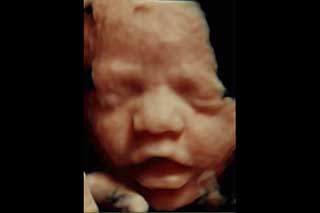

Ecografias en 4d

Reconstrucción Digital 3d en tiempo real, visualización de los movimientos fetales, bostezos, sonrisas, etc.

La ecografía 3D es aquella que permite a usted ver la superficie corporal de su bebé, esto permite observar detalles como: labios, nariz, pómulos, frente, manos, entre otras.

Para lograr esto es necesario que se cumplan muchas condiciones como por ejemplo que el bebé no este mirando hacia atrás, que la placenta, el cordón o las extremidades no le tapen su rostro, así como que el líquido amniótico esté en cantidad suficiente.